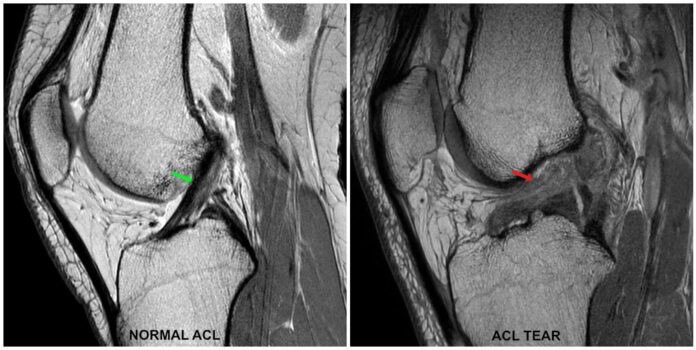

A partial ACL tear is usually diagnosed during an examination. Your doctor will feel for any tears and look at your knee’s ligament.

Partial ACL tears occur when the anterior cruciate ligament (ACL) is partially torn. The ACL is a large, fan-shaped ligament in the knee that helps stabilize the knee joint and prevent excessive knee motion.

The ACL is the major ligament that stabilizes the knee. It provides stability to the knee and prevents it from sliding out of place. If the ACL is torn, the knee is unstable, which makes it difficult to perform athletic movements such as jumping or running.